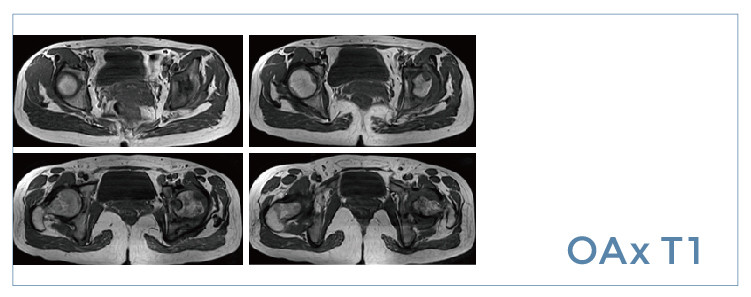

【朗润影像档案】20190809磁共振影像病例结果讨论